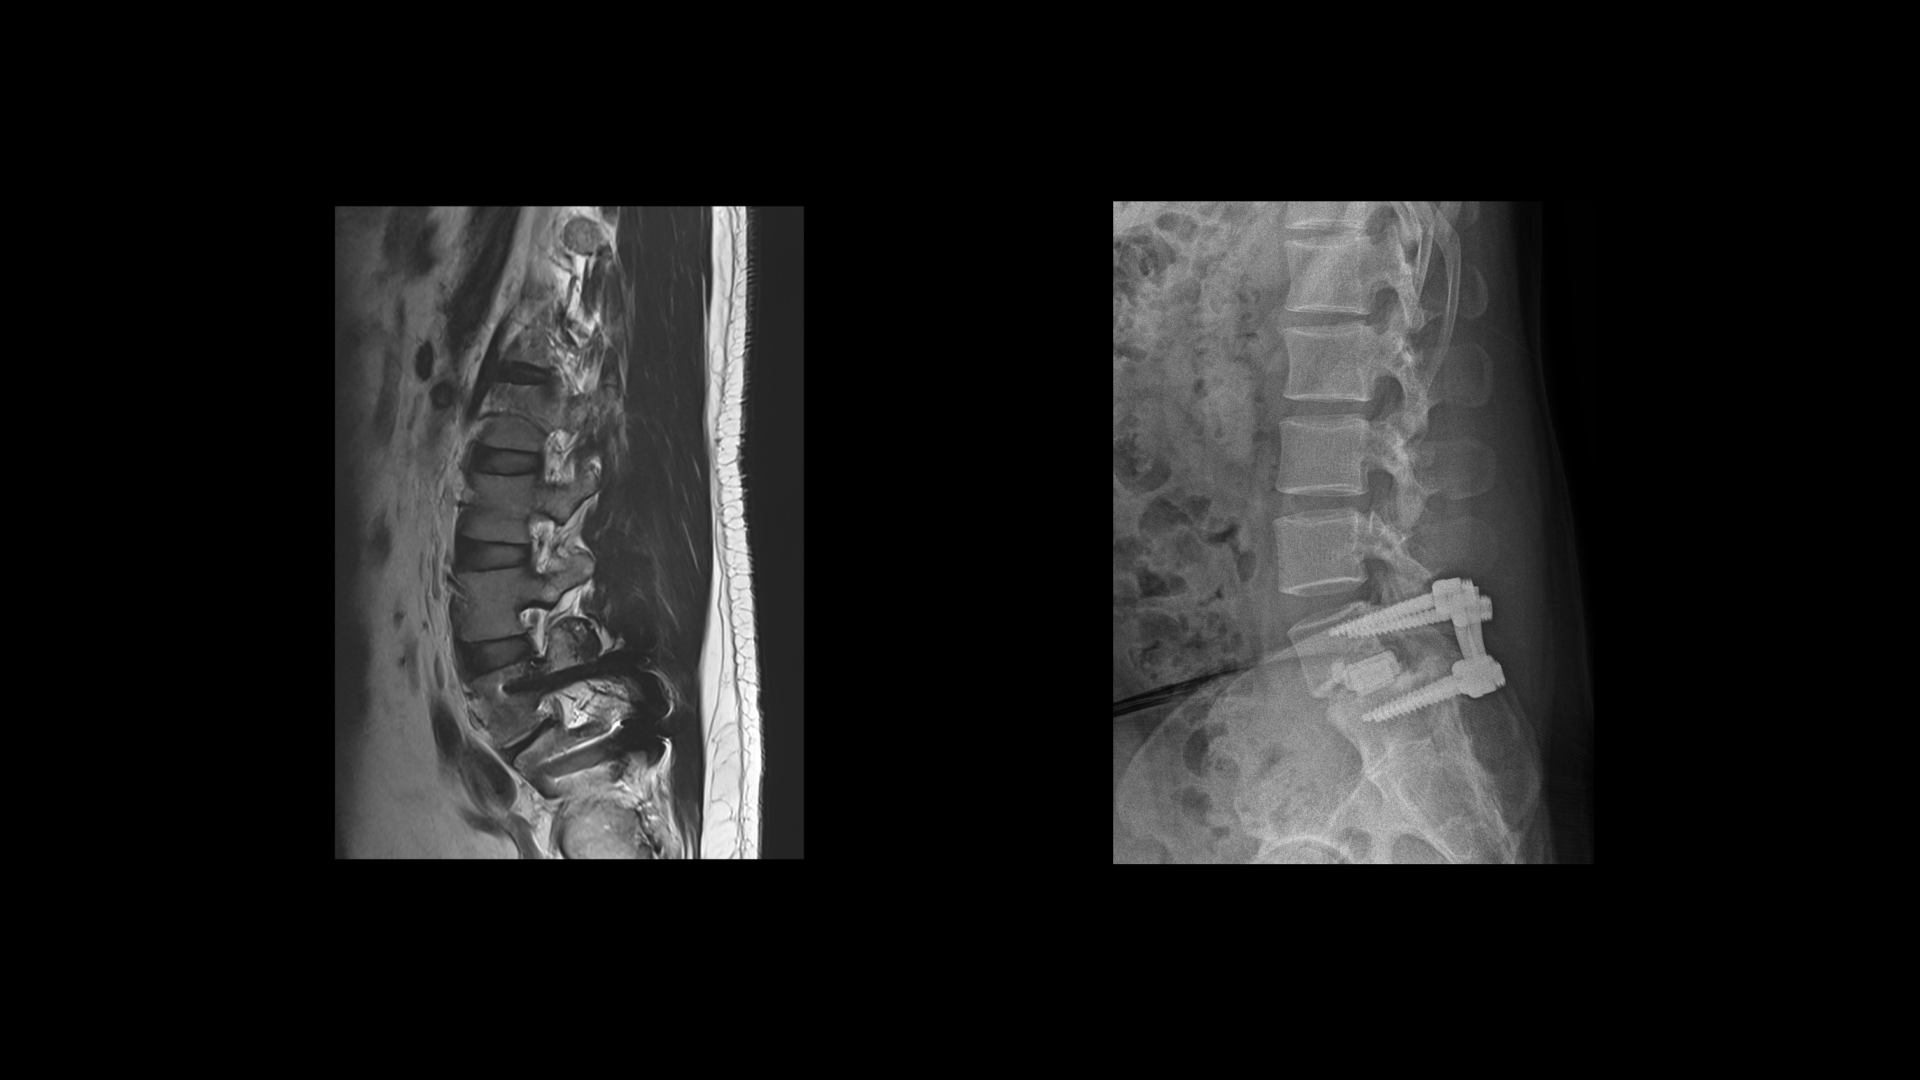

이분은 21살 때 척추분리증과 허리디스크 파열로 척추유합술을 받았습니다.

수술은 깨끗하게 잘 되었다는 얘기를 들었고 실제로 수술 후 2년간은 괜찮았습니다. 그러나 수술 후 2년이 지나면서 점점 허리, 엉덩이, 골반 부위가 뭉치면서 아파지고 계속 심해져서 결국 종아리와 발목까지 아프게 되었고 누웠다 일어나기도 힘들고 허리를 구부리는 것도 힘들고 오래 걷기도 어려워졌습니다. 대학병원에서는 약 처방 외에는 해줄 게 없다고 했고 다른 척추 병원들은 시술이나 주사치료를 하라고 해서 받았지만 효과는 제한적이었습니다.

그런데 척추유합술 후 또는 척추감압술 후 이렇게 아픈 환자분들이 매우 많습니다. 척추수술 후에 아픈 이유는 여러 가지가 있을 수 있지만 이 환자분은 명확하게 신경의 문제가 아닙니다. 첫째, 수술 직후 2년간 결과가 좋았었고, 그건 신경 감압이 잘 되었고 신경 감압 효과가 즉시 잘 나타났다는 의미입니다. 또 2년 후에 다시 아픈 이유도 우리가 흔히 얘기하는 인접 분절 질환도 아닙니다. 척추유합술을 하고 나면 몇 년 후에 수술 부위 위나 아래 마디에서 문제가 생기는 경우가 많습니다. 그걸 인접분절질환이라고 합니다. 그런데 이 환자분은 보시다시피 위 마디의 디스크도 깨끗합니다. 그럼 무슨 이유로 아픈 걸까요? 당연히 근육 문제입니다.

눌린 신경이 깨끗이 잘 풀려 있으면 근육 문제 외에 다른 문제를 생각하기 어렵습니다. 수술 후에 허리 유합으로 인한 허리 기능이 떨어지고 수술로 인한 허리 근육 손상도 있기 때문에 허리 근육과 골반, 엉덩이 쪽 근육들이 뭉치고 굳으면서 상태가 안 좋아지니까 결국 아래쪽의 종아리와 발끝까지도 아픈 겁니다.

이 환자분 말씀 잘 들으셨나요? 아프기는 하지만 기존의 치료해왔던 방법으로는 해결이 전혀 안되기에 절박한 심정으로 속는 셈치고 저희 모커리를 방문하셨다고 했습니다. 척추수술 후에 계속 아픈데도 신경문제라 생각하고 신경주사만 계속 맞고 계신 분들이 많습니다. 척추수술 후 통증의 원인을 계속 신경에서 찾고 있는 것이죠. 그래서 눌린 신경을 풀어주는 수술은 잘 됐으니 신경이 회복될 때까지 6개월에서 1년 정도 기다려 보라는 얘기를 듣는 경우가 많습니다. 그러나 수술이 잘 됐다면 수술 후에도 계속 아픈 이유는 근육일 가능성이 훨씬 더 높습니다. 근육이 뭉치고 아픈 기능적 문제는 MRI에서 보이지 않기 때문에 수술 후 허리 주변 근육, 골반, 엉덩이, 다리 근육들이 뭉치고 굳고 뒤틀리면서 아픈 것은 근육을 직접 만져보지 않는 한 알 수가 없습니다.

그런데도 근육은 전혀 만져보지 않고 MRI, X-ray만 보면서 수술은 잘 됐으니 아프면 약 먹고 신경주사만 맞고 무작정 기다리는 겁니다. 이 환자분은 당연히 허리 유합술로 인해 허리 주변 근육이 심하게 뭉쳐 있고 굳어 있는 상태였습니다. 유합술을 한 환자의 허리 근육을 만져 보면 특유의 수술로 인한 상처 조직 때문에 섬유화 되고 굳은 듯한 느낌이 있는데 이 환자분 역시 허리 근육이 많이 굳어 있고 좌우의 뭉치고 굳은 정도의 차이도 컸습니다. 골반과 엉덩이, 다리 근육들도 많이 뭉쳐 있는 상태였구요. 수술 후 통증은 반드시 이런 허리, 골반, 엉덩이, 다리 근육들을 만져보고 뭉치고 굳어있고 아픈 근육들을 직접 치료해주면 통증이 훨씬 더 빨리 사라질 수 있습니다.